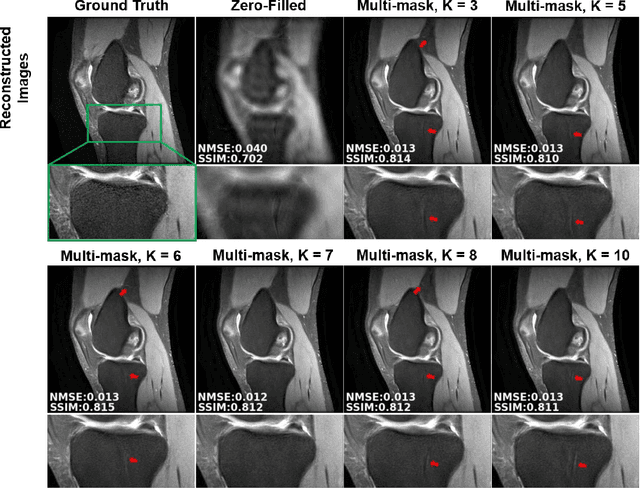

Abstract:Purpose: To develop an improved self-supervised learning strategy that efficiently uses the acquired data for training a physics-guided reconstruction network without a database of fully-sampled data. Methods: Currently self-supervised learning for physics-guided reconstruction networks splits acquired undersampled data into two disjoint sets, where one is used for data consistency (DC) in the unrolled network and the other to define the training loss. The proposed multi-mask self-supervised learning via data undersampling (SSDU) splits acquired measurements into multiple pairs of disjoint sets for each training sample, while using one of these sets for DC units and the other for defining loss, thereby more efficiently using the undersampled data. Multi-mask SSDU is applied on fully-sampled 3D knee and prospectively undersampled 3D brain MRI datasets, which are retrospectively subsampled to acceleration rate (R)=8, and compared to CG-SENSE and single-mask SSDU DL-MRI, as well as supervised DL-MRI when fully-sampled data is available. Results: Results on knee MRI show that the proposed multi-mask SSDU outperforms SSDU and performs closely with supervised DL-MRI, while significantly outperforming CG-SENSE. A clinical reader study further ranks the multi-mask SSDU higher than supervised DL-MRI in terms of SNR and aliasing artifacts. Results on brain MRI show that multi-mask SSDU achieves better reconstruction quality compared to SSDU and CG-SENSE. Reader study demonstrates that multi-mask SSDU at R=8 significantly improves reconstruction compared to single-mask SSDU at R=8, as well as CG-SENSE at R=2. Conclusion: The proposed multi-mask SSDU approach enables improved training of physics-guided neural networks without fully-sampled data, by enabling efficient use of the undersampled data with multiple masks.